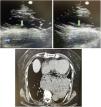

This is the case of a 78-year-old woman with a 2-h history of intense oppressive chest pain associated with sweating and poor general condition. The examination of the patient’s heartbeats reveals a visible and overt vibration at thoracic wall level. The bedside echocardiography performed in the parasternal view—both in the long (figure 1) and short axes (figure 2)—revealed the presence of extrinsic compression of the heart by a fluid-and-air-filled heart chamber (in blue color) that caused the protrusion of the heart lower side (in green color). The CCTA performed discards the presence of acute aortic disease but confirms the presence of massive hiatal hernia with complete herniation of the gastric chamber (figure 3) (Fig. 1).